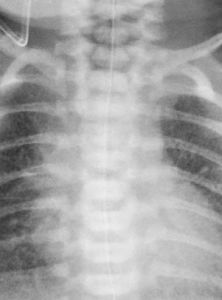

2.X線檢查

肺部病變廣泛多樣,但吸收快,大部分4天內消失。

(1)肺泡積液症兩肺野密度淡而均勻的斑片狀陰影,可融合成片或成結節狀。

(2)肺氣腫由部分肺泡呈代償性膨脹所致。

(3)肺間質積液可見血管和細支氣管周圍增寬的條狀陰影。

(4)葉間和/或胸腔積液多為右側葉間胸膜腔積液。

(5)肺紋理增多和增粗因間質液的增加,使淋巴管和靜脈的轉運量增加,造成淋巴管和靜脈擴張。

5.X線檢查可見兩側肺野透明度較低,肺紋理增多,增粗及斑點狀密度增深的陰影,有時可見葉間或胸腔積液,因代償性肺氣腫而於肺野出現廣泛而散在的小透亮區,胸廓前後徑增寬,橫膈頂扁平並降低,第2天以後連續攝片時可見這些異常迅速恢復正常,其表現與體徵不成正比。